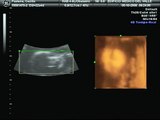

Polémica tras el aborto realizado a mujer con siete meses de gestación